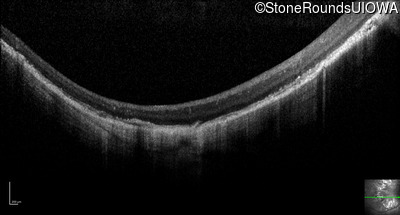

Optical Coherence Tomography - Right - 20/200 +1

Exemplar / OCT Stack

OCT Stack